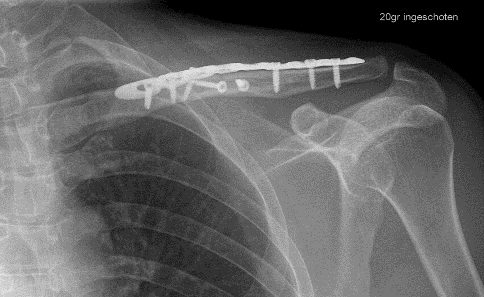

U bent onder behandeling bij Amsterdam UMC omdat u uw sleutelbeen heeft gebroken. Afhankelijk van het soort breuk van uw sleutelbeen, heeft uw traumachirurg in overleg met u besloten de breuk met of zonder operatie te behandelen. In deze folder krijgt u informatie over de behandeling en het herstel na een gebroken sleutelbeen, met of zonder operatie.